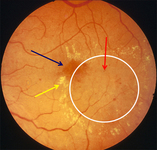

Non-proliferative diabetic retinopathy with macular oedema: exudate (yellow arrow), microaneurysms (red arrow), thickened retina (white circle), cystic change at macula (blue arrow)

Courtesy of Moorfields Photographic Archive; used with permission